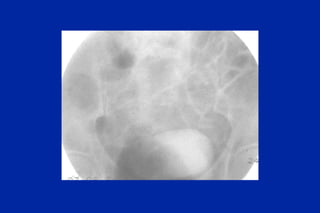

Este documento resume los principales tipos y técnicas de angiografía. Describe brevemente la angiografía, arteriografía, flebografía y linfografía, así como las técnicas de contraste y materiales utilizados. También explica los principales accesos vasculares, la técnica de Seldinger, la angiografía por sustracción digital y algunas técnicas endovasculares comunes.